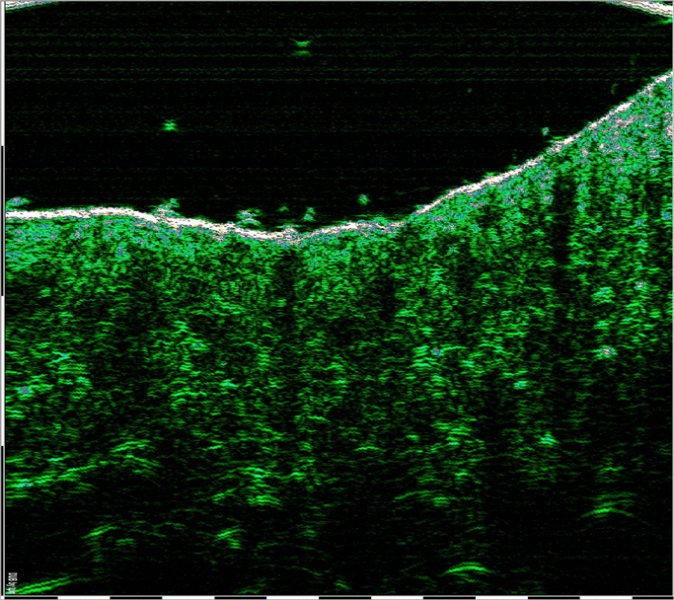

W celu oceny skuteczności terapii z wykorzystaniem fibryny bogatopłytkowej I-PRF oraz S-PRF przeprowadzono badania gęstości akustycznej skóry przed i po podaniu obu frakcji. Zabieg polegał na podaniu fibryny komórkowej i strukturalnej w okolice łuku jarzmowego u pacjentki (62 l.)

Ultrasonografia wysokiej częstotliwości rzędu 75 MHz – HFUS (HIGH FREQUENCY ULTRASOUND) – jest metodą pozwalającą w bezpieczny sposób obrazować wszystkie warstwy skóry. Badanie HFUS pozwala ocenić jej grubość, strukturę wewnętrzną czy zawartość włókien kolagenowych.

Przed zabiegiem u wykonano pomiar gęstości skóry za pomocą głowicy ultrasonograficznej o częstotliwości 75 MH, w miejscach poddanych zabiegowi. Wykonano dokumentację fotograficzną skanów ultrasonograficznych. Na podstawie wykonanych pomiarów dokonano oceny gęstości akustycznej skóry, jako parametru określającego zmianę gęstości tkanki skórnej poddanej terapii.

Pomiar gęstości skóry wykonany przy pomocy DUB SkinScanner , mgr inż. Symon Korzekwa.

Poniższe obrazy ultrasonograficzne: [1], [2], przedstawiają zmianę gęstości akustycznej skóry w obszarze łuku jarzmowego.

Gęstość akustyczna jest to zdolność tkanki do odbicia fali ultradźwiękowej. Jest to skala bezwzględna znormalizowana w zakresie od 0 -255.

Rys. [1] Przed zabiegiem – Gęstość 20 Rys. [2] Po zabiegu – Gęstość 66

W wykonanym obrazowaniu, stwierdzono bardzo charakterystyczny trend wzrostowy gęstości skóry właściwej po podaniu fibryny I-PRF oraz S-PRF. Ten efekt widoczny jest również po drugim zabiegu, czyli po 2 miesiącach terapii.